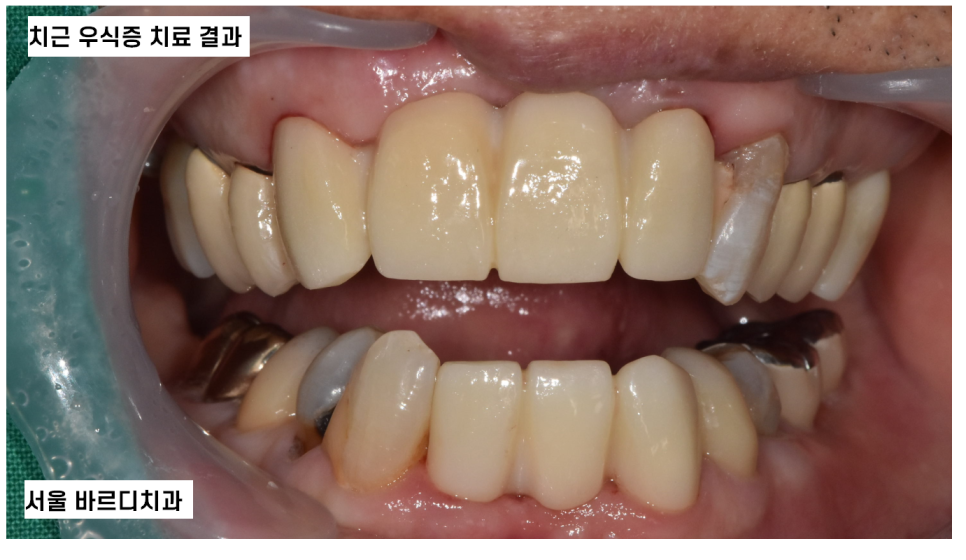

오늘 서울바르디치과를 내원하신 환자분은

입 마름으로 인하여 다발성 치근 우식증이 있었는데요.

뒤늦게 내원하셔서 증상이 심각하였고

(이미 부러진 치아도 있었어요ㅠㅠ)

신경치료 후 보철 치료로 진행할 수밖에 없었답니다.